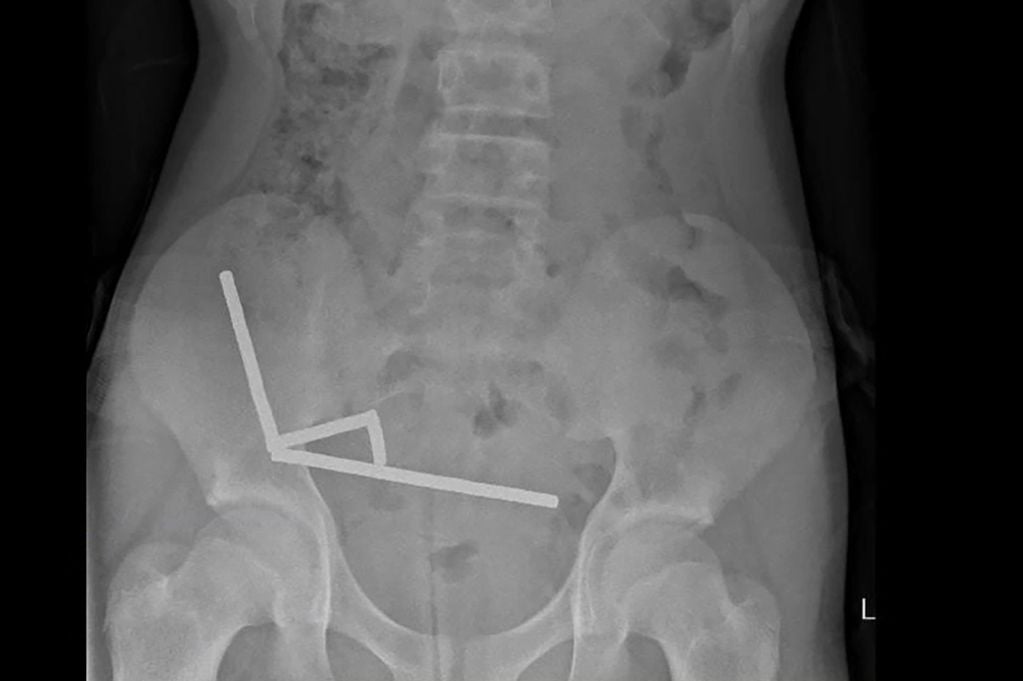

แม่เหล็กกำลังสูง (Neodymium) เหล่านี้ถูกสั่งซื้อมาจาก Temu ซึ่งเป็นแพลตฟอร์มตลาดออนไลน์สัญชาติจีน โดยแม่เหล็กรูปทรงเม็ดเล็กๆ ได้ดูดติดกันเป็ แถบยาว 4 แถบ อยู่ภายในลำไส้เล็กและลำไส้ใหญ่ของเด็กชาย

“แถบแม่เหล็กเหล่านี้ดูเหมือนจะติดกันในส่วนที่แยกกันของลำไส้ เนื่องมาจากแรงแม่เหล็ก” รายงานระบุ แรงกดดันจากการดูดติดกันทำให้เกิดภาวะเนื้อตาย (Necrosis) ในลำไส้เล็กและลำไส้ใหญ่ถึงสี่บริเวณ